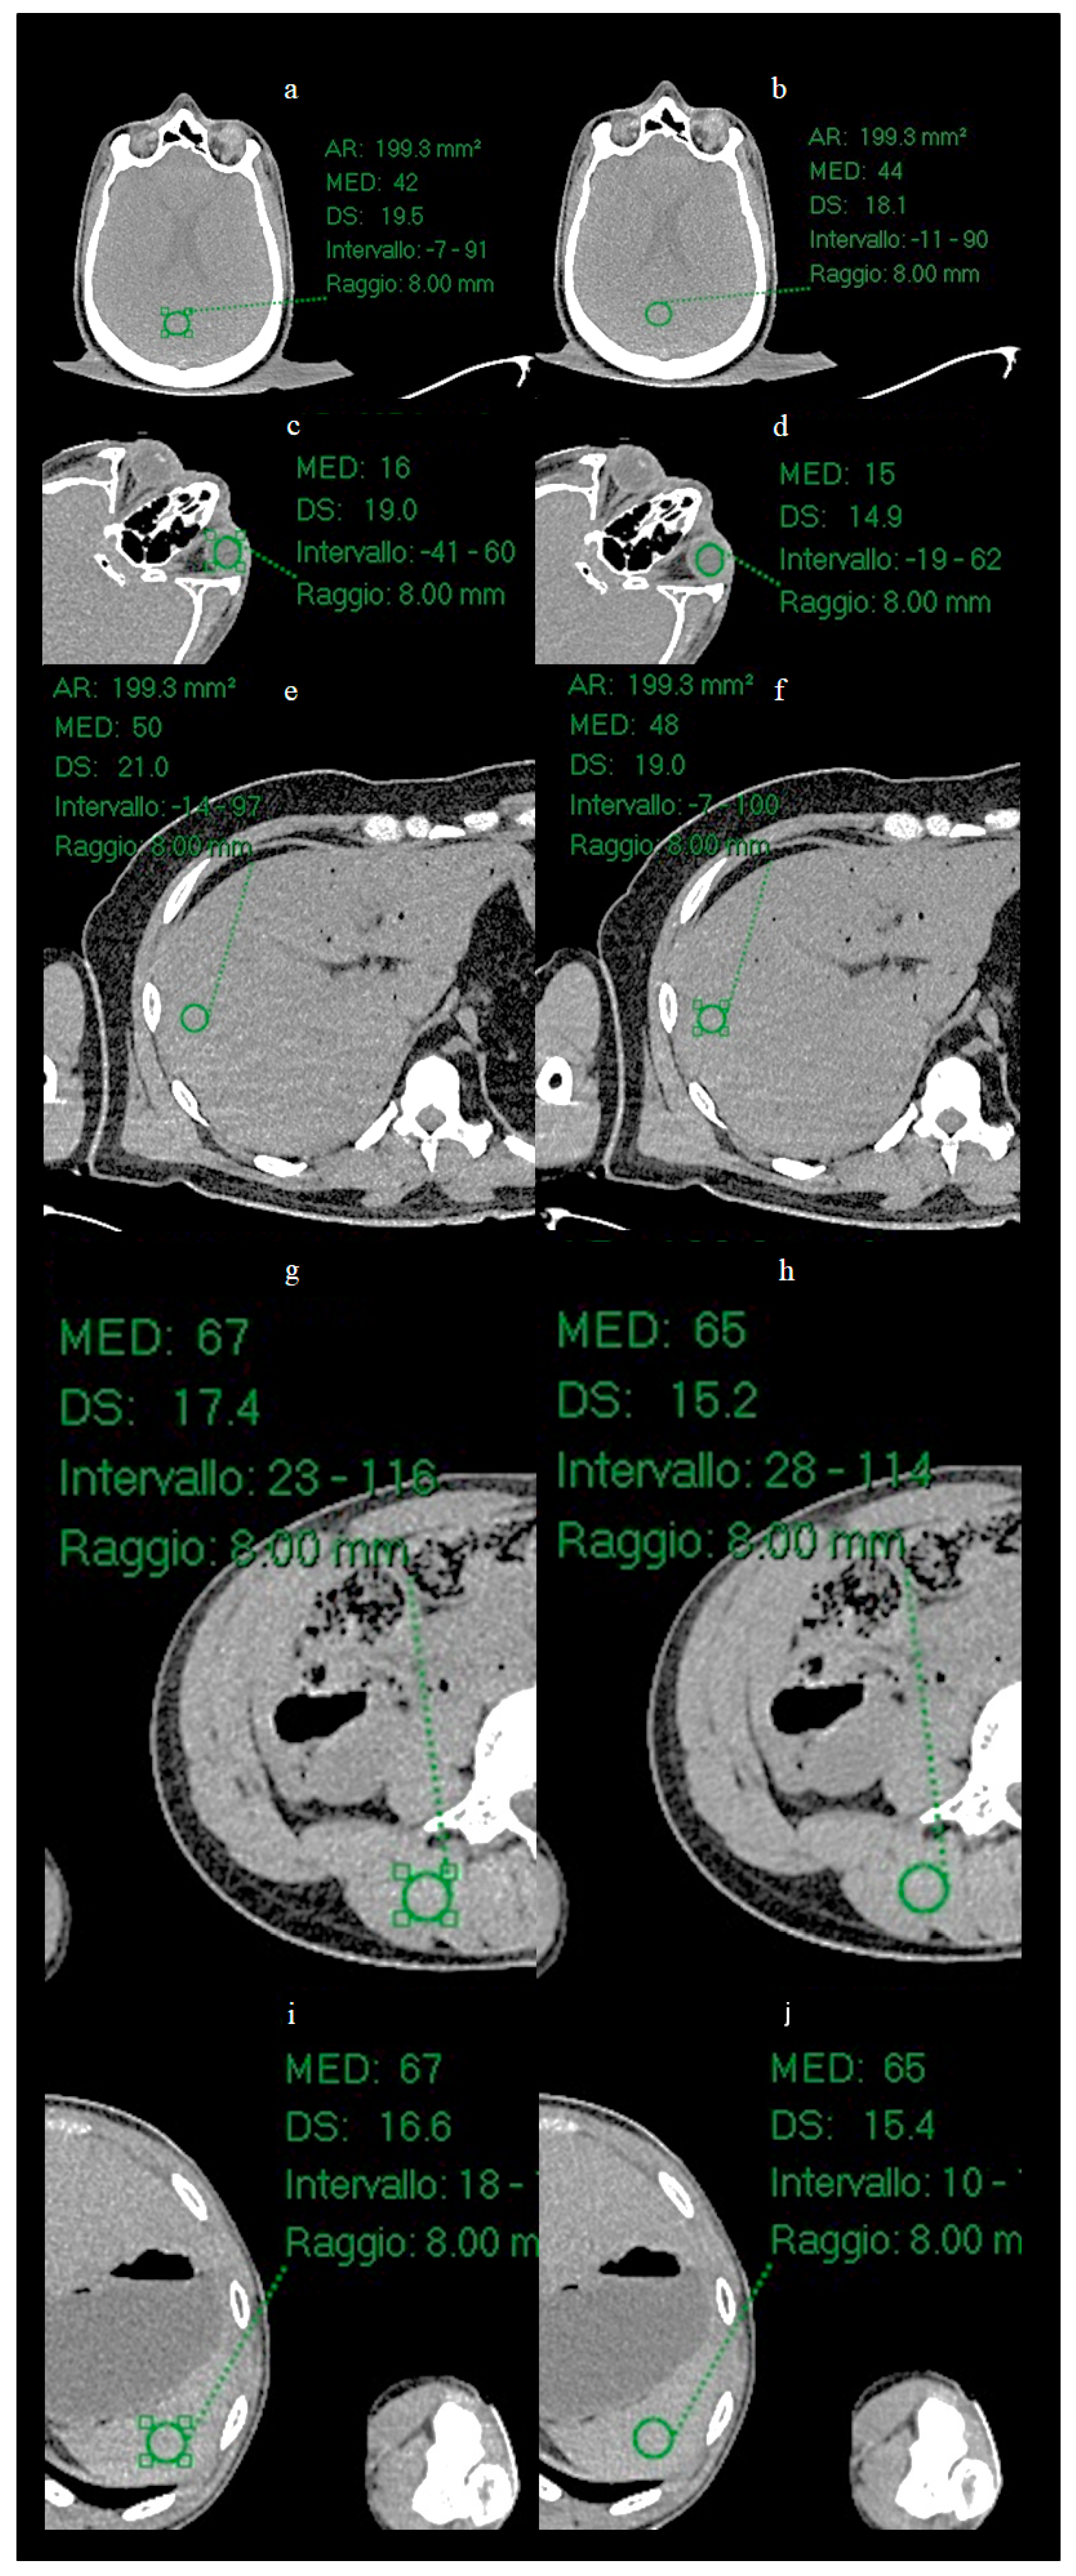

In the present study, a quantitative noise analysis was also performed by applying circular regions of interest (ROI) (radius 8 mm) at five anatomical locations (Figure 3): vitreous body, brain parenchyma, liver parenchyma, splenic parenchyma and paravertebral muscle. Within each ROI, the mean and standard deviation (SD) of the attenuation values (Hounsfield units) were calculated in order to characterize and compare the noise level before and after processing with ErisNet.

Figure 3.

ROI placement at five anatomical locations for quantitative analysis. Circular green ROIs with radius 8 mm were positioned on: (a) liver parenchyma, (b) splenic parenchyma, (c) vitreous body of the eye, (d) brain parenchyma, and (e) lumbar paravertebral muscle. These anatomical regions were selected to evaluate ErisNet performance across different tissue types and attenuation characteristics.

3.2. ROI Results

Circular ROI of radius 8 mm were placed on the images of the Test Set on the vitreous body (Figure 6), brain parenchyma, liver parenchyma, splenic parenchyma and paravertebral muscle, and the mean and SD of the mean values of Hounsfield Units (HU) were calculated for each ROI.

Figure 6.

Positioning of ROIs in five anatomical locations for quantitative analysis. Circular ROIs with a radius of 8 mm were placed on: (a,b) brain parenchyma, (c,d) vitreous body of the eye, (e,f) liver parenchyma, (g,h) lumbar paravertebral muscle, and (i,j) spleen parenchyma. For each anatomical location, the image on the left shows the low-dose acquisition, while the image on the right shows the corresponding result processed by ErisNet. These anatomical regions were selected to evaluate ErisNet’s performance on different tissue types and attenuation characteristics. The comparison demonstrates a consistent reduction in the standard deviation of Hounsfield units within the ROIs after processing with ErisNet (Table 4).

The mean values of measured ROI are shown in Table.